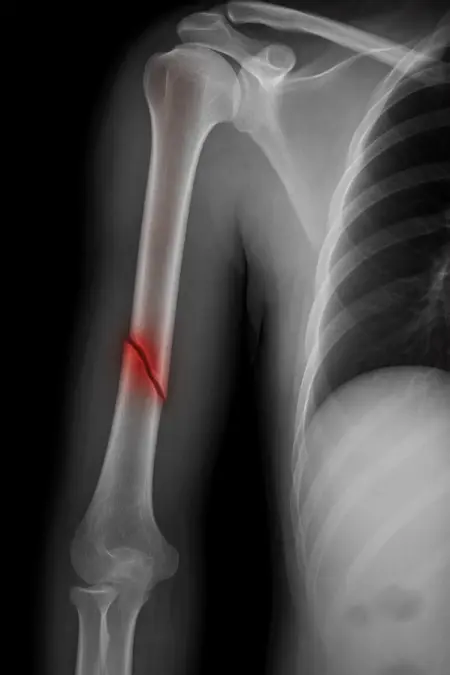

アートや写真の編集用に設計されたFlux Kontextのようなモデルを、医療画像、たとえば「単純な」骨折の赤色マーキングに使用できるか?

即答:面白い結果を出すが、過剰に反応し、医療ツールとしては信頼性に欠ける。これはアイデアを試すためのプロトタイプに過ぎない。

テスト結果:

- 偽陽性 ≈ 24%

- 骨折検出 ≈ 20%

感度モード(検出を優先、ノイズ多め)

- Euler、15ステップ、Karras

- Denoise:1.0

結果:

- 偽陽性 ≈ 80%

- 骨折検出 ≈ 86%

さらに攻撃的な設定(例:rk beta57、Denoise 1.0)では、**偽陽性100%、検出100%**という馬鹿げた結果に:すべてを赤で塗りつぶし、健常部もほぼすべて骨折と誤認する。未経験の目には区別がつかない。